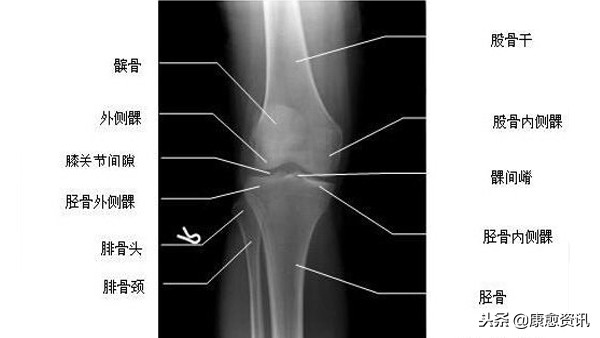

膝部骨折包括股骨下段骨折、股骨髁骨折、髌骨骨折、胫骨髁间骨折、胫骨平台骨折、胫骨上段骨折,不包括膝关节置换、半月板损伤、内外侧副韧带损伤、交叉韧带损伤。